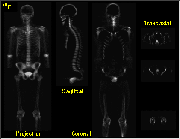

Click on image above to view full-size image.

Whole-body image data can be reconstructed and displayed in 2-D projection views, as well as transaxial, coronal and sagittal tomographic views. These images can be displayed individually or in an interactive cine mode, allowing for the analysis of overlying structures.

Shown above are 18F- scans (single image; cinematic view) in sagittal and coronal cross-sections. The acquisition time for a whole-body image set is approximately one hour, and proportionally less for more anatomically focused studies. The whole-body PET display formats facilitate comparison with anatomic imaging studies such as X-ray CT and MRI.